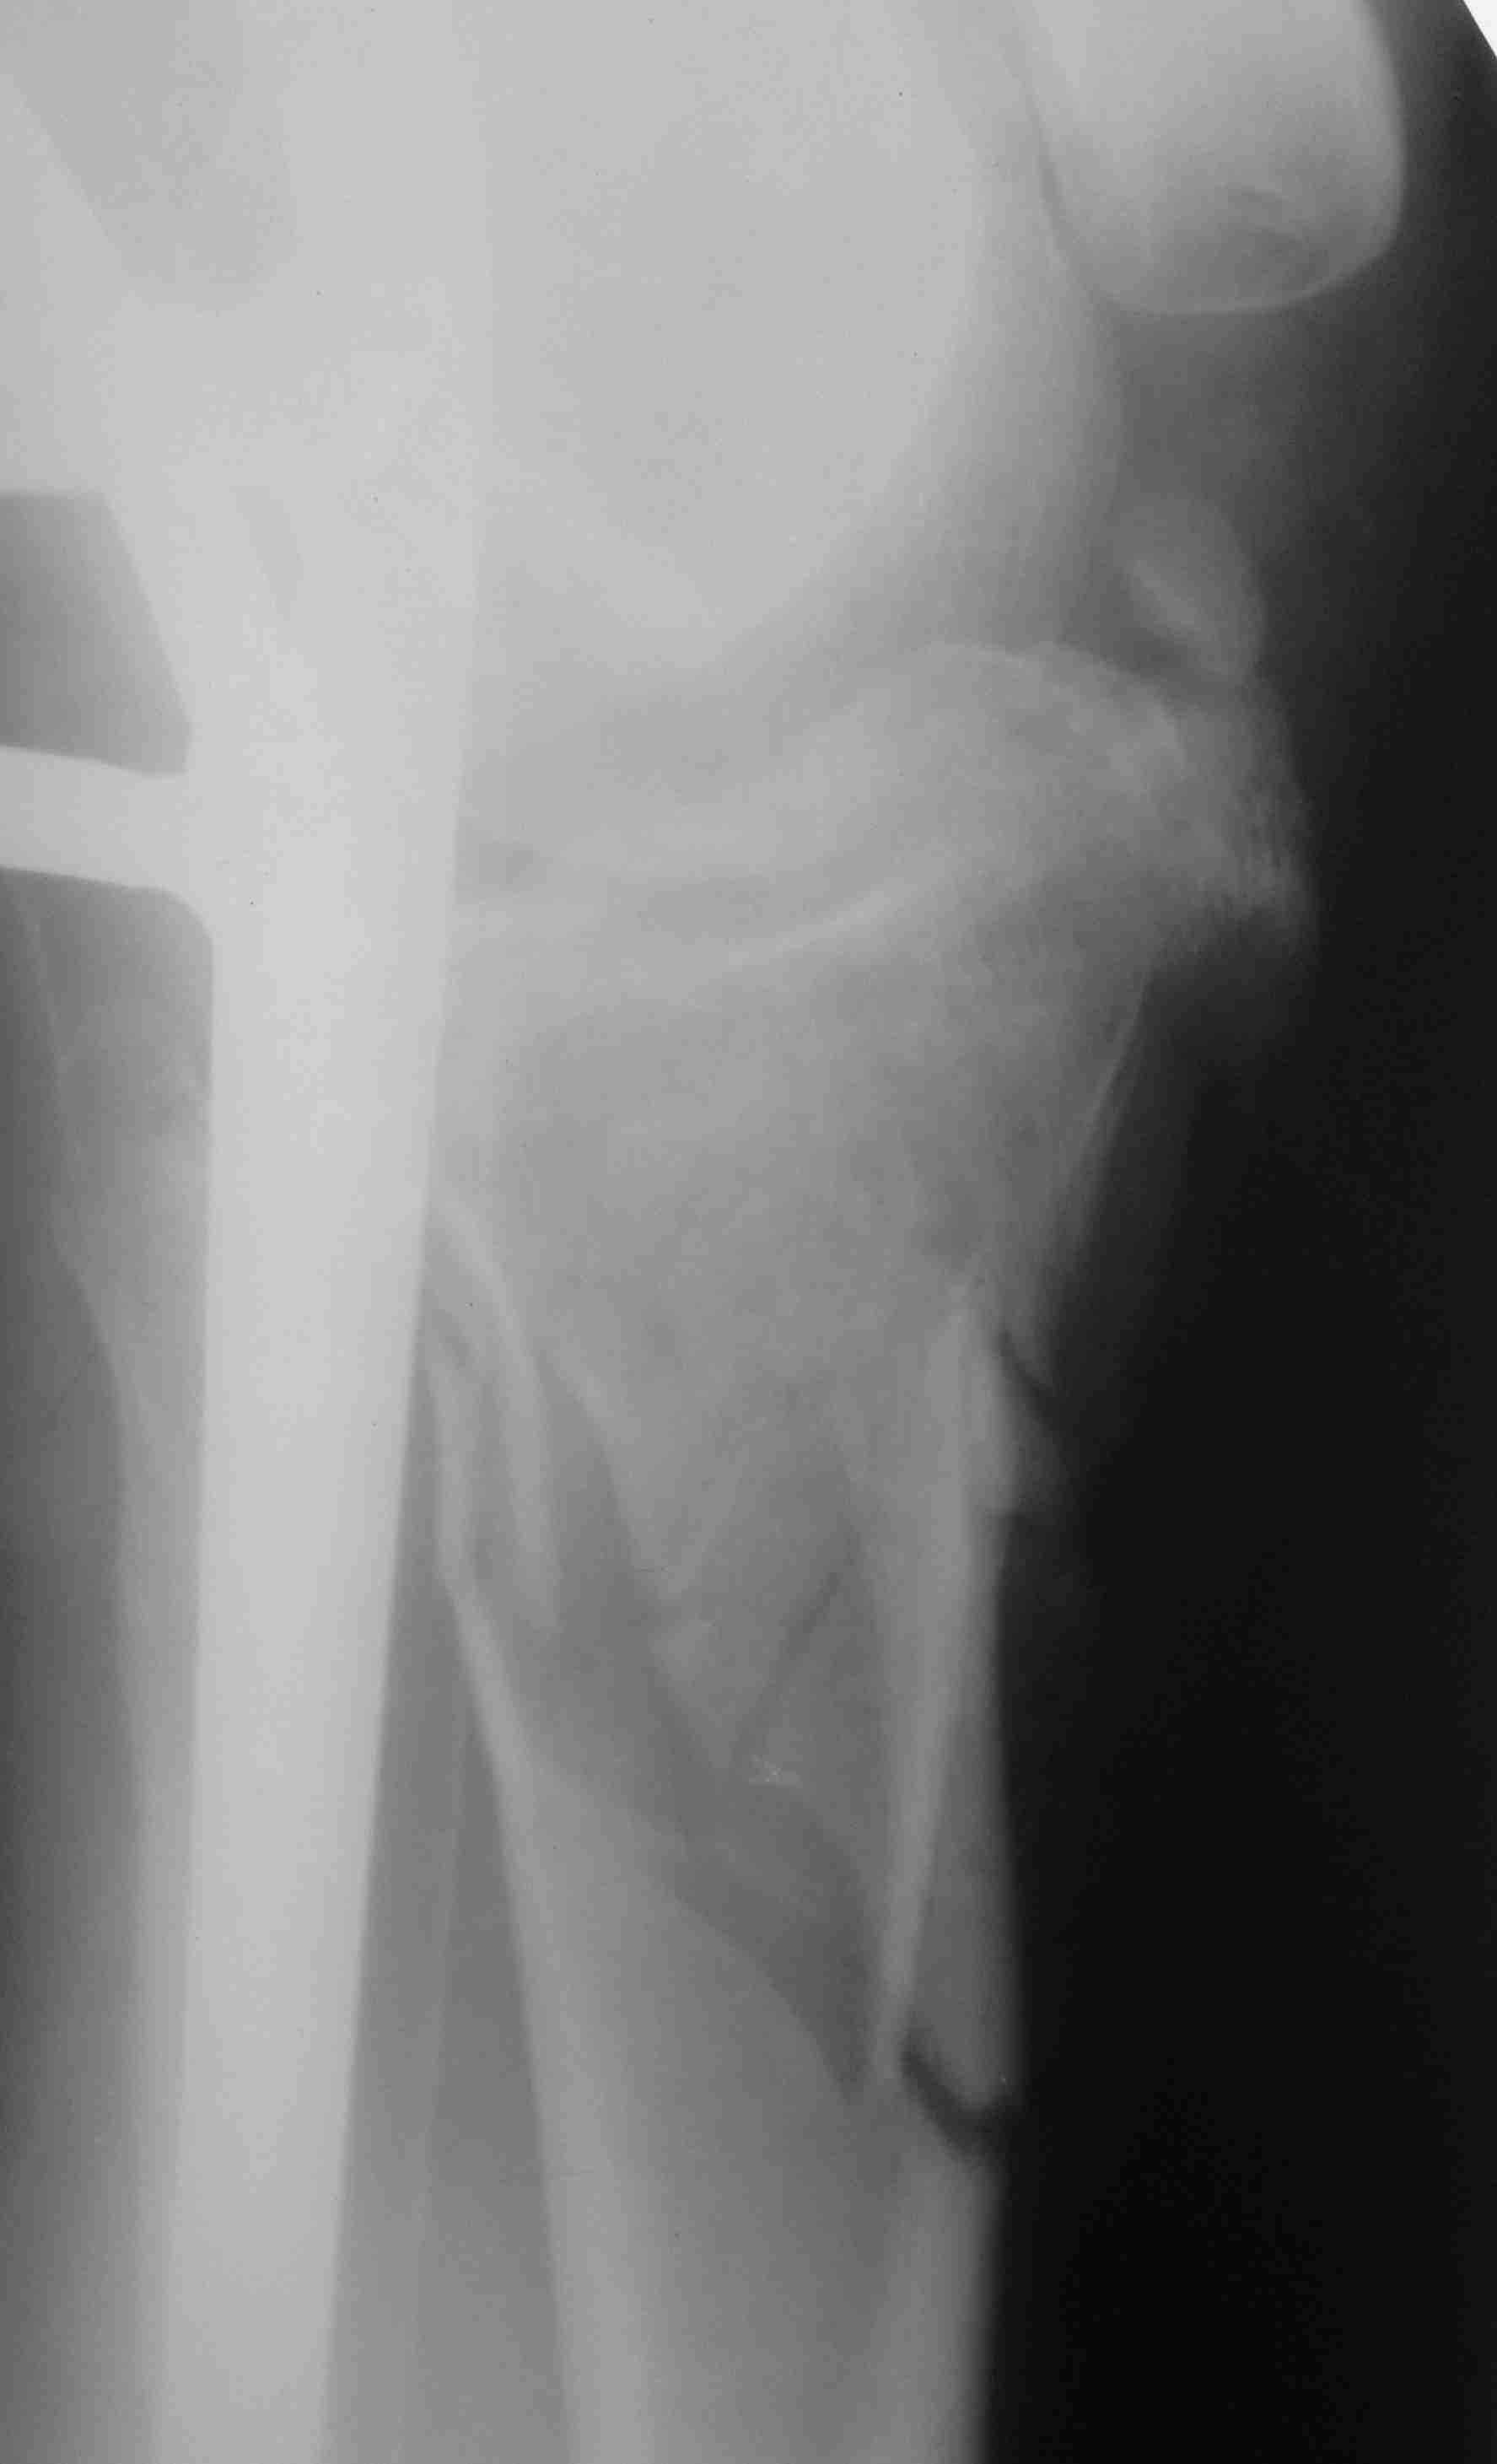

[Ortho] перелом проксимальной тибии + вывих бедра

Высокоэнергетическая травма около недели назад, мужчина 39 лет

По месту поступления вывих бедра вправлен, ПХО раны открытого перелома

б/б кости, скелетное вытяжение. В настоящее время рана заживает неплохо,

небольшое количество серозно-геморрагического отделяемого, состояние

мягких тканей неплохое. Планируем остеосинтез плато из 2-х доступов по

заживлению раны.

1 смущает фрагмент плато в проекции раны, насколько удобно его будет

ловить, попробовать полечить в аппарате + винты

закрыто?

2 часть задней стенки в суставе, такое впечатление, что она больше ямки

и подвывихивает сустав или это ошибочное впечатление?

3. насколько целесообразно искать этот фрагмент во впадине и пытаться

засинтезировать задний край при наличии довольно выраженного FAI?